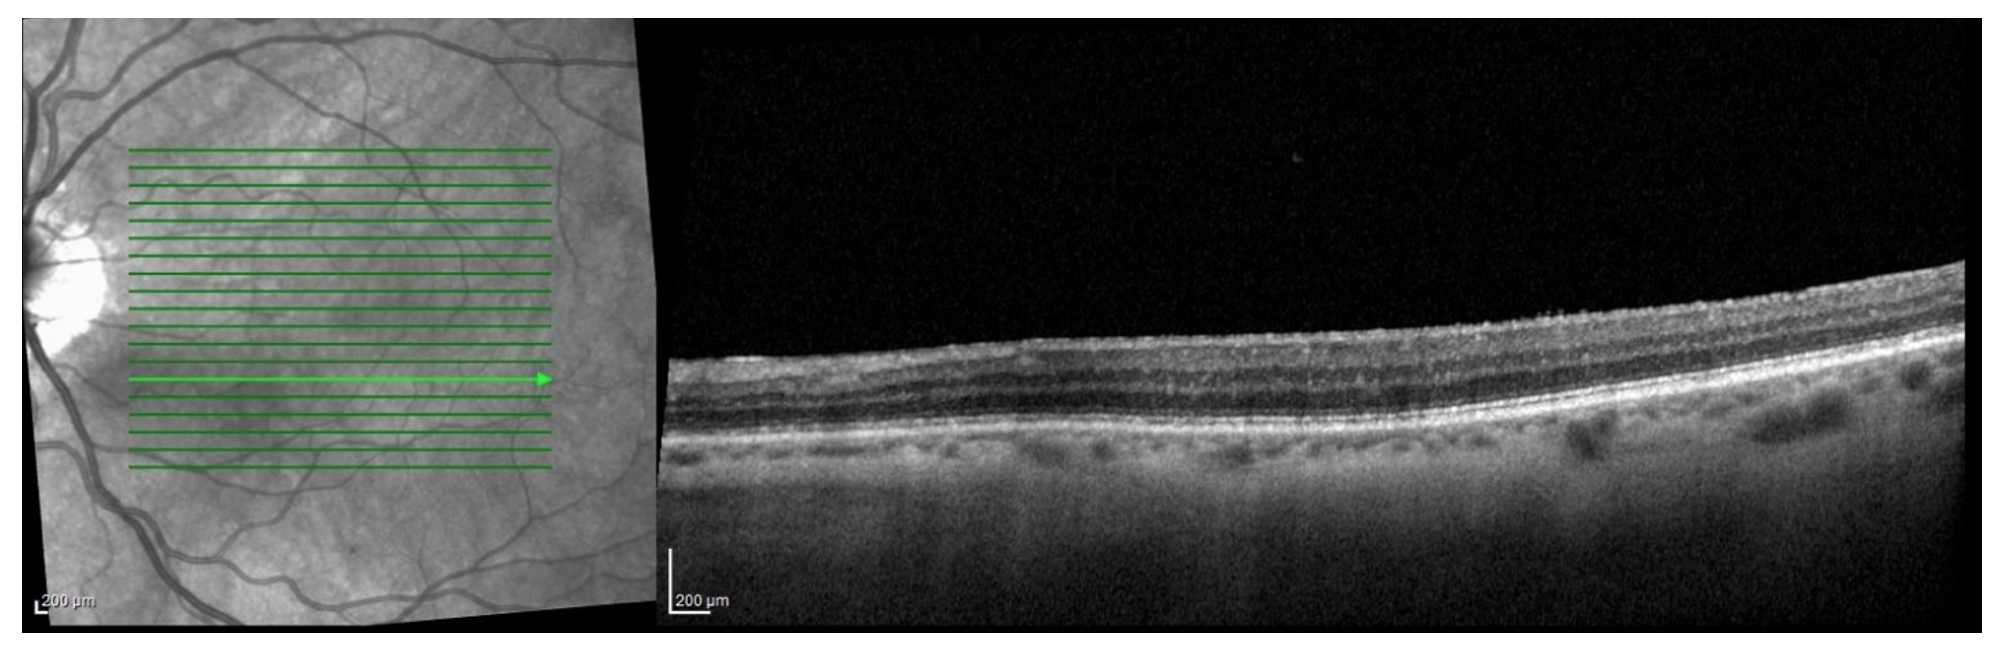

A 77-year-old female with history of cataracts, HTN, HLD, DM2, and aortic stenosis presents for new spots in the left eye. She denies flashes of light, photophobia and new floaters. Visual acuity is 20/40 OU (uncorrected) and anterior segment exam demonstrates trace nuclear sclerosis OU without vitreous cell in either eye. What is the diagnosis? What other diagnoses should be considered? How would you manage this patient?